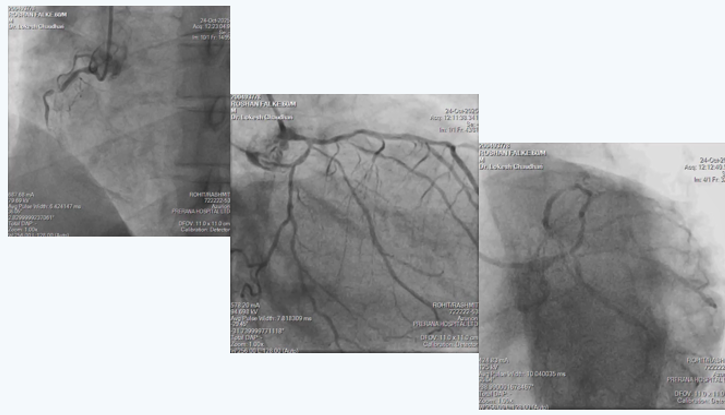

On arrival had mild dyspnea, no chest discomfort but had severe right lower limb pain since 6 hours, hence was started on heparin infusion and bilateral lower limb CT peripheral angiography was done which revealed Bilateral lower limb severe peripheral vascular disease with occlusion in bilateral femoral arteries and distal reformation through collaterals. Gradually patient was stabilized with heparin infusion alone. After 5 days, creatinine came to baseline of 1.5 and angiography wad done which showed Critical Left main with Triple vessel disease as shown in angiogram pictures. Patient had Right coronary artery in-stent-chronic total occlusion with filling of distal RCA from collaterals from LCA; Distal Left main had 80% narrowing with proximal LAD 70% and proximal LCX 80% stenosis.

In view of multiple comorbidities and patients preference, high risk complex multi-vessel PCI (Including RCA-ISR-CTO & LM-LAD-LCX bifurcation) was planned and done as per plan under local anesthesia from right radial artery access as CT aerogram showed diffuse peripheral vascular disease starting from abdominal aorta extending into bilateral femoral arteries.